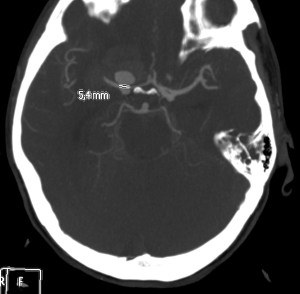

Se decide realizar Angio-TC.

Estamos ante una Hemorragia Subaracnoidea por rotura aneurismática.

El 85% de las hemorragias espontáneas en el espacio subaracnoideo son debidas a la ruptura de un aneurisma. Se deben a la evaginación de la íntima y la adventicia, la clave es la ausencia de lámina elástica interna y capa muscular. Se da en el 1% de la población y entre el 2-30% pueden ser múltiples. El 90% de los aneurismas cerebrales se localizan en la circulación anterior, los localizados en la ACM dan la típica imagen de hiperdensidad en las cisternas basares cuando se rompen.

Angiografía- TC: Se basa en la TC de cortes helicoidales. Aunque implica radiación para el paciente y requiere administración de contraste iodado intra-venoso (no requiere cateterización arterial), el hecho de que posea gran disponibilidad y sea una técnica rápida y fácil de llevar a cabo en pacientes enfermos, hace que se use como prueba de primera línea. Se puede realizar con cortes de 1 mm y realizaremos reconstrucciones para obtener imágenes como las de una angiografía (cine + MIP).

Debido al riesgo de resangrado, se indican los TC de control en pacientes con HSA aneurismática. Además, la realización de un Segundo y Tercer angio TC en pacientes con patrón aneurismático, ha permitido la detección de aneurismas que se habían pasado por alto.